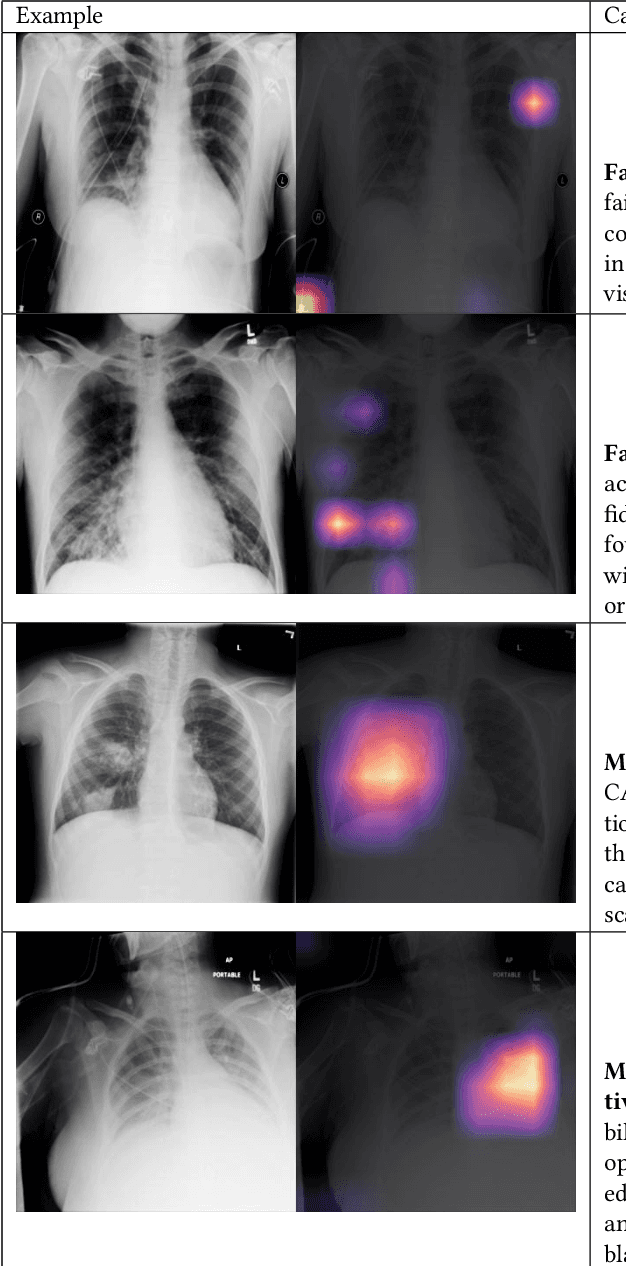

Abstract:Motivation: Traditional image attribution methods struggle to satisfactorily explain predictions of neural networks. Prediction explanation is important, especially in the medical imaging, for avoiding the unintended consequences of deploying AI systems when false positive predictions can impact patient care. Thus, there is a pressing need to develop improved models for model explainability and introspection. Specific Problem: A new approach is to transform input images to increase or decrease features which cause the prediction. However, current approaches are difficult to implement as they are monolithic or rely on GANs. These hurdles prevent wide adoption. Our approach: Given an arbitrary classifier, we propose a simple autoencoder and gradient update (Latent Shift) that can transform the latent representation of an input image to exaggerate or curtail the features used for prediction. We use this method to study chest X-ray classifiers and evaluate their performance. We conduct a reader study with two radiologists assessing 240 chest X-ray predictions to identify which ones are false positives (half are) using traditional attribution maps or our proposed method. Results: We found low overlap with ground truth pathology masks for models with reasonably high accuracy. However, the results from our reader study indicate that these models are generally looking at the correct features. We also found that the Latent Shift explanation allows a user to have more confidence in true positive predictions compared to traditional approaches (0.15$\pm$0.95 in a 5 point scale with p=0.01) with only a small increase in false positive predictions (0.04$\pm$1.06 with p=0.57). Accompanying webpage: https://mlmed.org/gifsplanation Source code: https://github.com/mlmed/gifsplanation